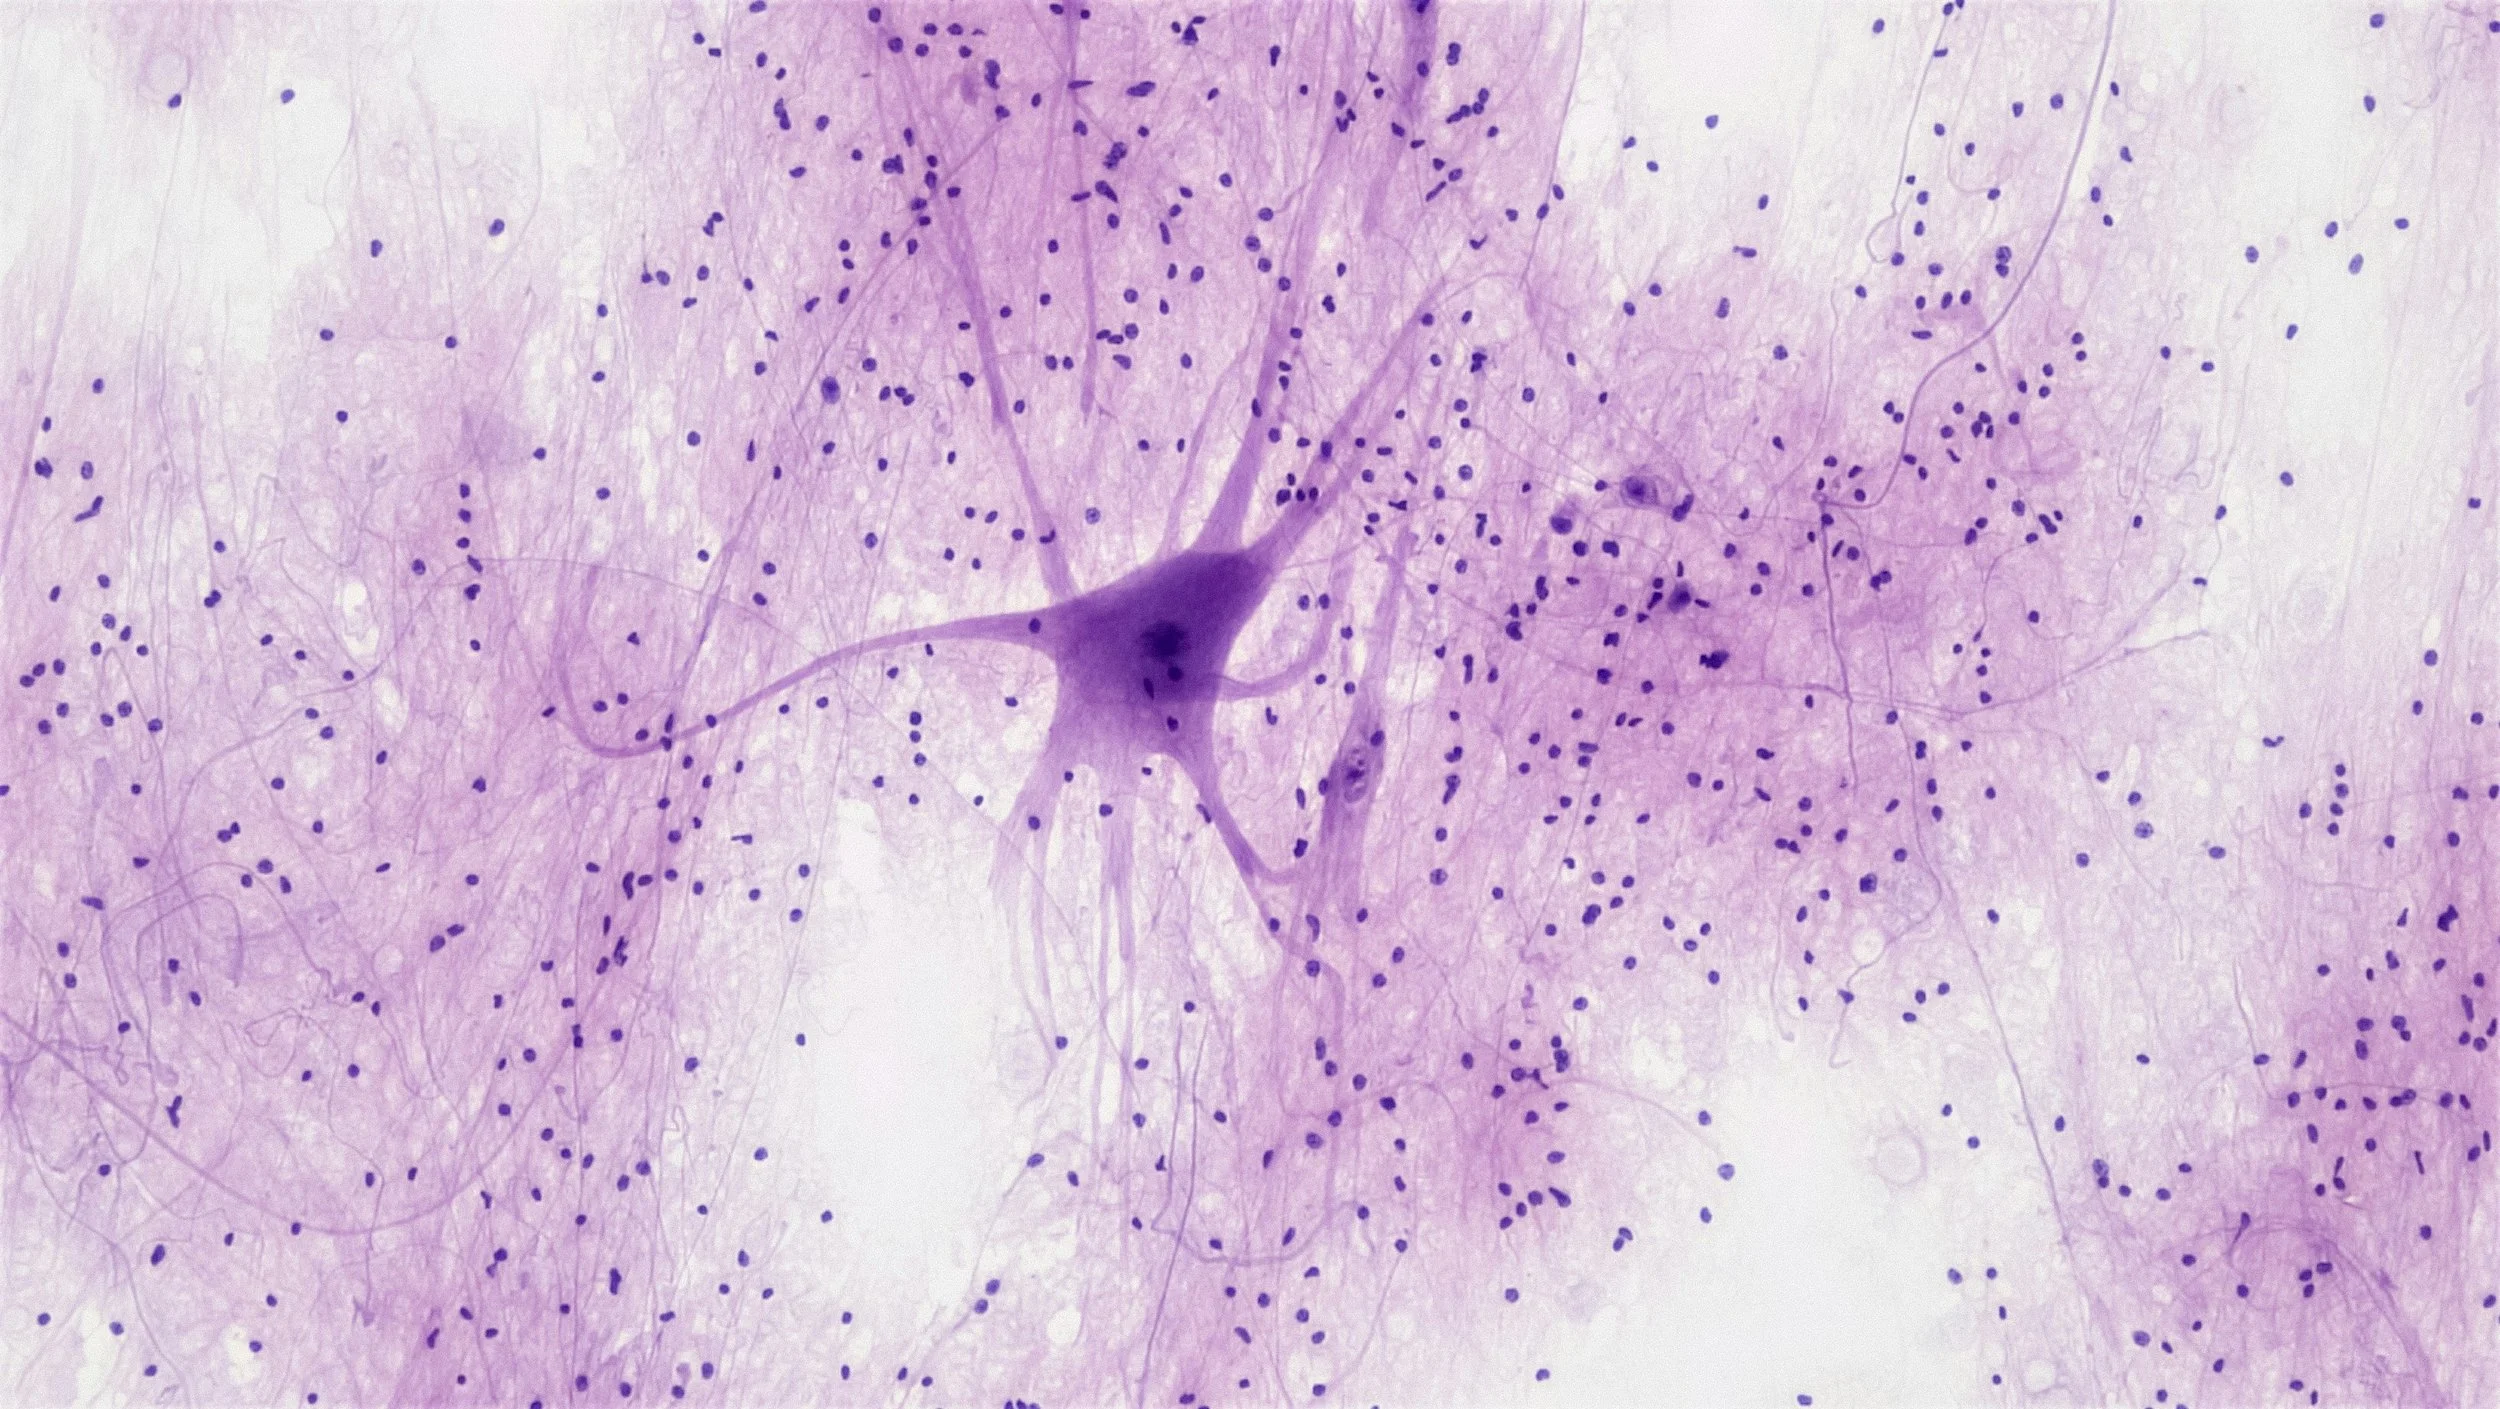

New research from La Jolla Institute for Immunology (LJI) and Columbia University Irving Medical Center (CUIMC) reveals that there may be an autoimmune component to amyotrophic lateral sclerosis (ALS). ALS is a progressive neurodegenerative disease that affects neurons in the brain and spinal cord that control voluntary muscle movement. ALS is a devastating disease and tends to progress quickly, leading to loss of muscle control and eventual paralysis. Only around 10% of individuals diagnosed with ALS live with the disease for ten years or longer. Famous individuals diagnosed with ALS include Stephen Hawking and Lou Gehrig.

Researchers at LJI and CUIMC found that patients with ALS had a high number of inflammatory immune cells, called CD4+ T cells, that were mistakenly targeting a specific protein (called C9orf72) associated with the disease. This protein plays a role in the development and function of neurons in our body. The study also found that the immune system plays a key role in predicting patient survival times. Researchers found two distinct groups of patients with ALS, one with shorter survival times (like Lou Gehrig, who died 2 years after diagnosis) and the other with longer survival times (like Stephen Hawking, who lived for 55 years after his diagnosis).